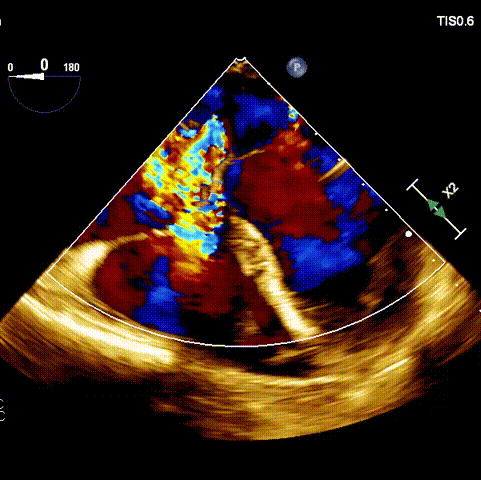

術(shù)前超聲

接受手術(shù)的為一名80歲男性,因“心悸2年,氣喘伴下肢水腫半年”入院。超聲心動提示“極重度三尖瓣反流,右房及右室明顯擴大,右心收縮功能輕度減低,左心收縮功能正常,肺動脈壓力正常”?;颊咄瑫r合并有“持續(xù)性房顫”及“慢性心力衰竭”,病史持續(xù)2年,規(guī)律口服抗凝及強心、利尿治療治療效果不佳,癥狀持續(xù)。經(jīng)廈心心臟團隊評估后,認(rèn)為患者三尖瓣極重度反流并伴有心衰表現(xiàn),長期內(nèi)科藥物治療效果不佳,且患者高齡、外科手術(shù)風(fēng)險高,因此決定采用微創(chuàng)經(jīng)頸靜脈LuX-Valve Plus三尖瓣置換系統(tǒng)為患者治療。